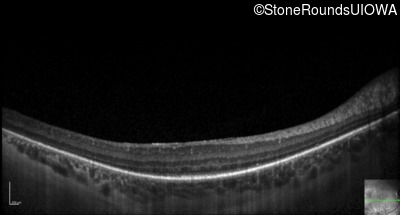

Optical Coherence Tomography - Right - 20/32 -1

Exemplar / OCT Stack

OCT Stack